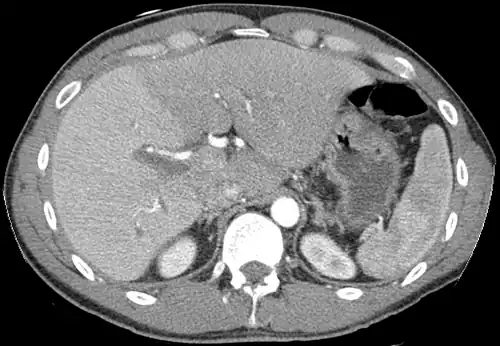

-

Axial CT image showing anomalous hepatic veins coursing on the liver's subcapsular anterior surface[74] -

A CT scan in which the liver and portal vein are shown